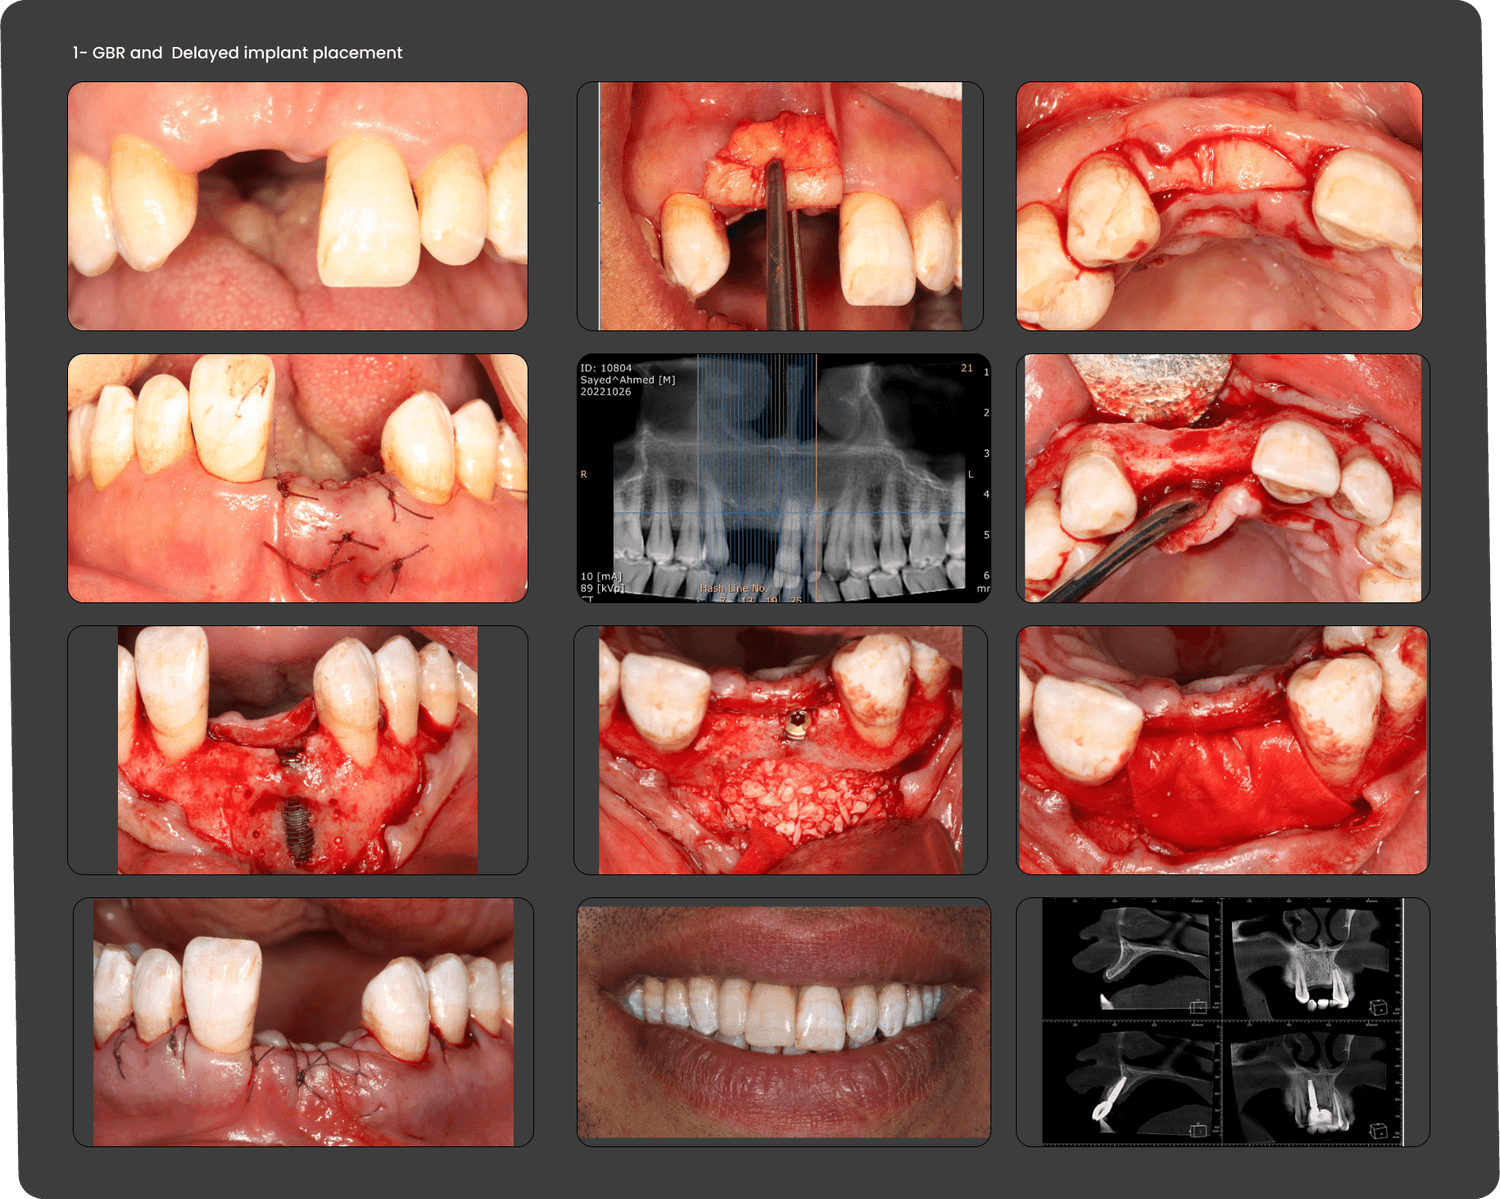

Note; la prima fase di questo caso e' stata realizzata da un altro paradontologo.